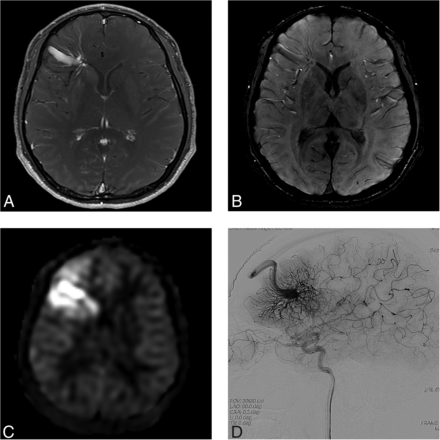

A 34-year-old woman presenting with a headache (case 6). A and B, Contrast-enhanced T1-weighted coronal MR imaging shows a DVA-like lesion in the bilateral parietal lobes. C, SWI demonstrates only hypointense signal in both the right (arrowheads) and left (arrow) lesions. D, The ASL quantitative CBF image demonstrates mildly hyperintense signal intensity in the parenchyma, corresponding to the location of the lesion. The left-sided lesion exhibits particularly subtle signal (arrows). E, In the late arterial phase of DSA, dilated medullary veins are gradually and subtly visualized (arrows). F, In the venous phase, dilated medullary veins draining to a collecting vein typical of a DVA are seen.